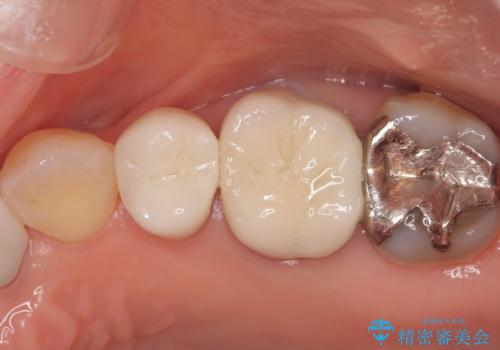

最終的な被せ物には、周囲の歯と自然になじむような色合い・透明感を持つセラミックを採用。形も元の歯に近づけ、違和感のない見た目と噛み心地を再現しました。

治療後には「見た目がきれいになって自信を持って笑えるようになった」「しみる症状もなくなり快適」とのお声をいただきました。虫歯治療はもちろん、古い被せ物による見た目の悩みも解決できる症例となりました。